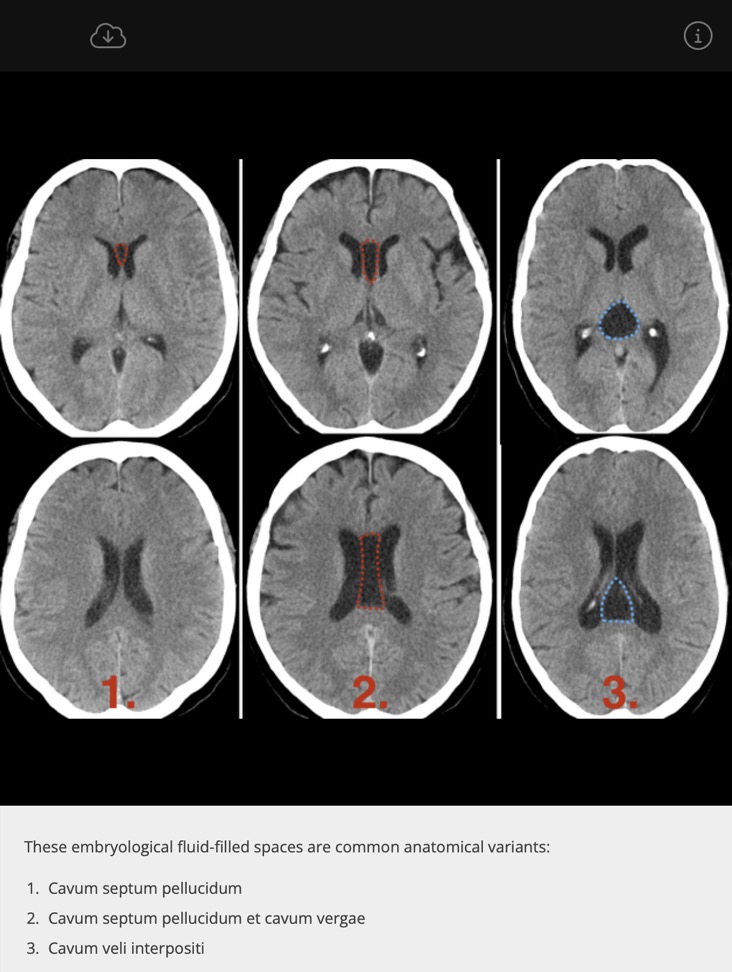

Kystes ligne médiane